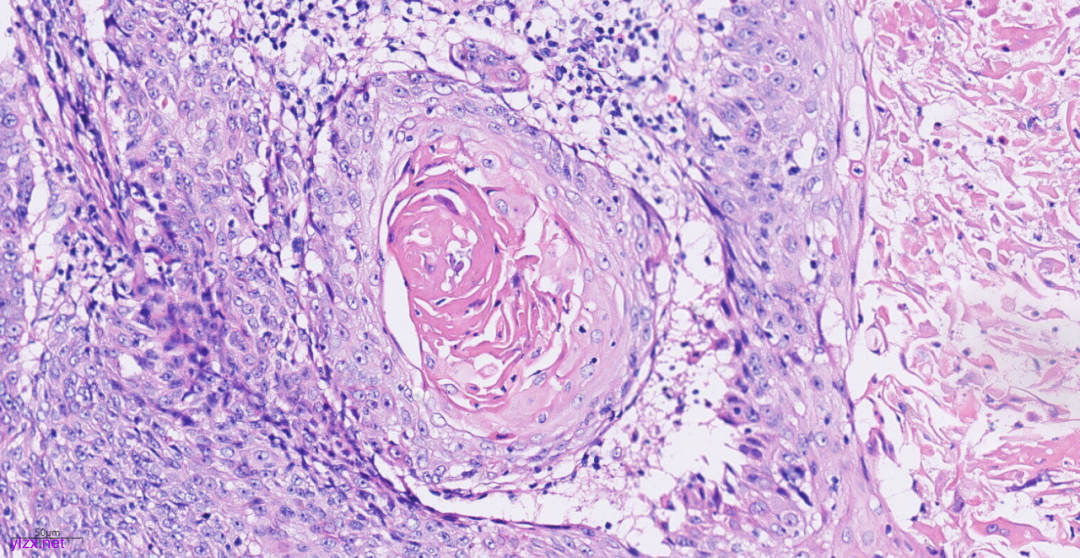

3.2镜下观(图3-图9):

低倍镜下可见卵巢肿物呈囊,中倍镜下,囊壁见分化成熟的多胚层成分,成熟型囊性畸胎瘤区域可见皮肤(正常鳞状上皮及其表明角化物)及其附属器成分(皮脂腺、汗腺及毛囊),局部囊壁表面可见由正常鳞状上皮-原位癌-鳞状细胞癌逐渐过渡;在鳞状细胞癌区域,囊壁增生的纤维结缔组织中可见肿瘤细胞呈巢状向下浸润性生长,也向囊腔内乳头状生长,局部癌巢中央可见角化珠及坏死;高倍镜下,鳞癌成分肿瘤细胞大小不等,细胞排列紊乱,细胞中-重度异型,核大深染,略呈空泡状,核仁明显,核分裂象易见,伴角化珠形成。

图7 高倍镜下,癌巢中央可见角化珠。